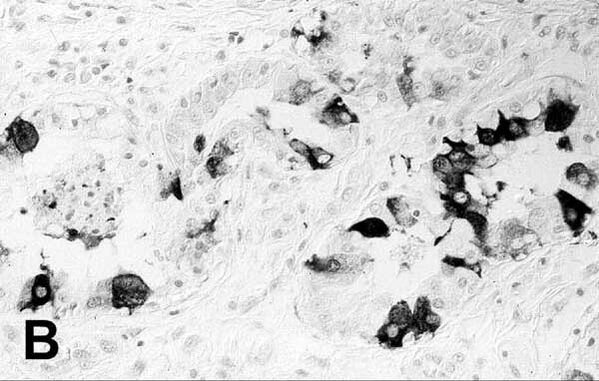

РНК-вирусы связаны с широким спектром заболеваний, включая многие из наиболее широко известных вирусных заболеваний. Известные болезнетворные вирусы Orthornavirae включают:[22]

Вирусы животных в Orthornavirae включают орбивирусы, которые вызывают различные заболевания у жвачных животных и лошадей, в том числе вирус катаральной лихорадки, вирус африканской чумы лошадей, вирус энцефалеза лошадей и вирус эпизоотической геморрагической болезни[24]. Вирус везикулярного стоматита вызывает заболевание крупного рогатого скота, лошадей и свиней[25]. Летучие мыши являются переносчиками многих вирусов, включая эболавирусы и генипавирусы, которые также могут вызывать заболевания у людей[26]. Аналогично, вирусы членистоногих родов Flavivirus и Phlebovirus многочисленны и часто передаются человеку[27][28]. Коронавирусы и вирусы гриппа вызывают заболевания у различных позвоночных, включая летучих мышей, птиц и свиней[29][30].